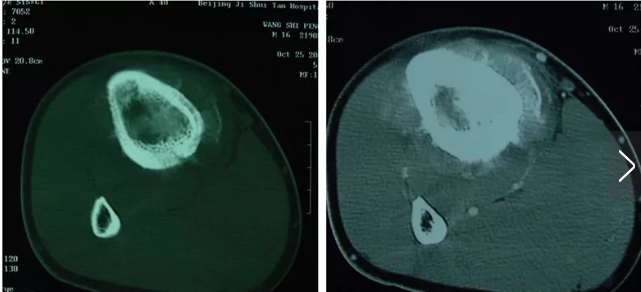

X線表現(xiàn)為侵襲性,破壞性和滲透性病損,能產(chǎn)生骨或骨樣組織。侵襲和破壞區(qū)的特征為X線透亮,分界不清楚,很快會破壞皮質(zhì)骨,進(jìn)入軟組織,但較少會跨越骨骺板和骨骺,進(jìn)入關(guān)節(jié)腔(圖1)。在皮質(zhì)骨穿透區(qū),可見反應(yīng)骨的Codman三角,而病損邊緣一般無反應(yīng)骨。病變的其他部位不完全礦化,有不定形的非應(yīng)力定向的瘤性骨。當(dāng)新生骨與長骨縱軸呈直角時,呈“日光放射線”狀,以前曾被認(rèn)定是骨肉瘤的獨(dú)特表現(xiàn)。后發(fā)現(xiàn)在其他一些惡性腫瘤也可有此表現(xiàn),因此,“日光放射線”并不是骨肉瘤的特有表現(xiàn)。

圖1.典型的骨肉瘤X線表現(xiàn)